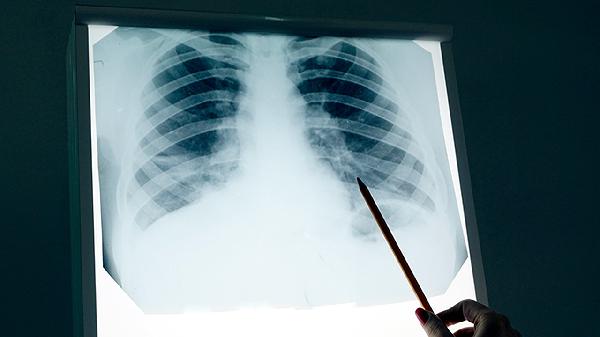

左肺舌叶纤维灶是什么意思

左肺舌叶纤维灶通常是指肺部影像学检查中发现的局部纤维化病变,可能由肺部感染、结核愈合后遗留或慢性炎症刺激导致。纤维灶属于陈旧性病变,多数无需特殊治疗,但需定期复查以排除活动性病变。